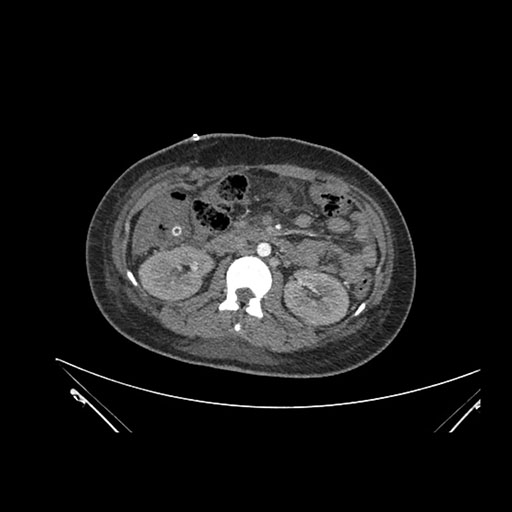

Imaging Analysis

Look through the patient's CT scan to identify any areas of concern for the necessary procedure.

Axial Venous

Based on initial findings, which issue(s) would you be most concerned about?